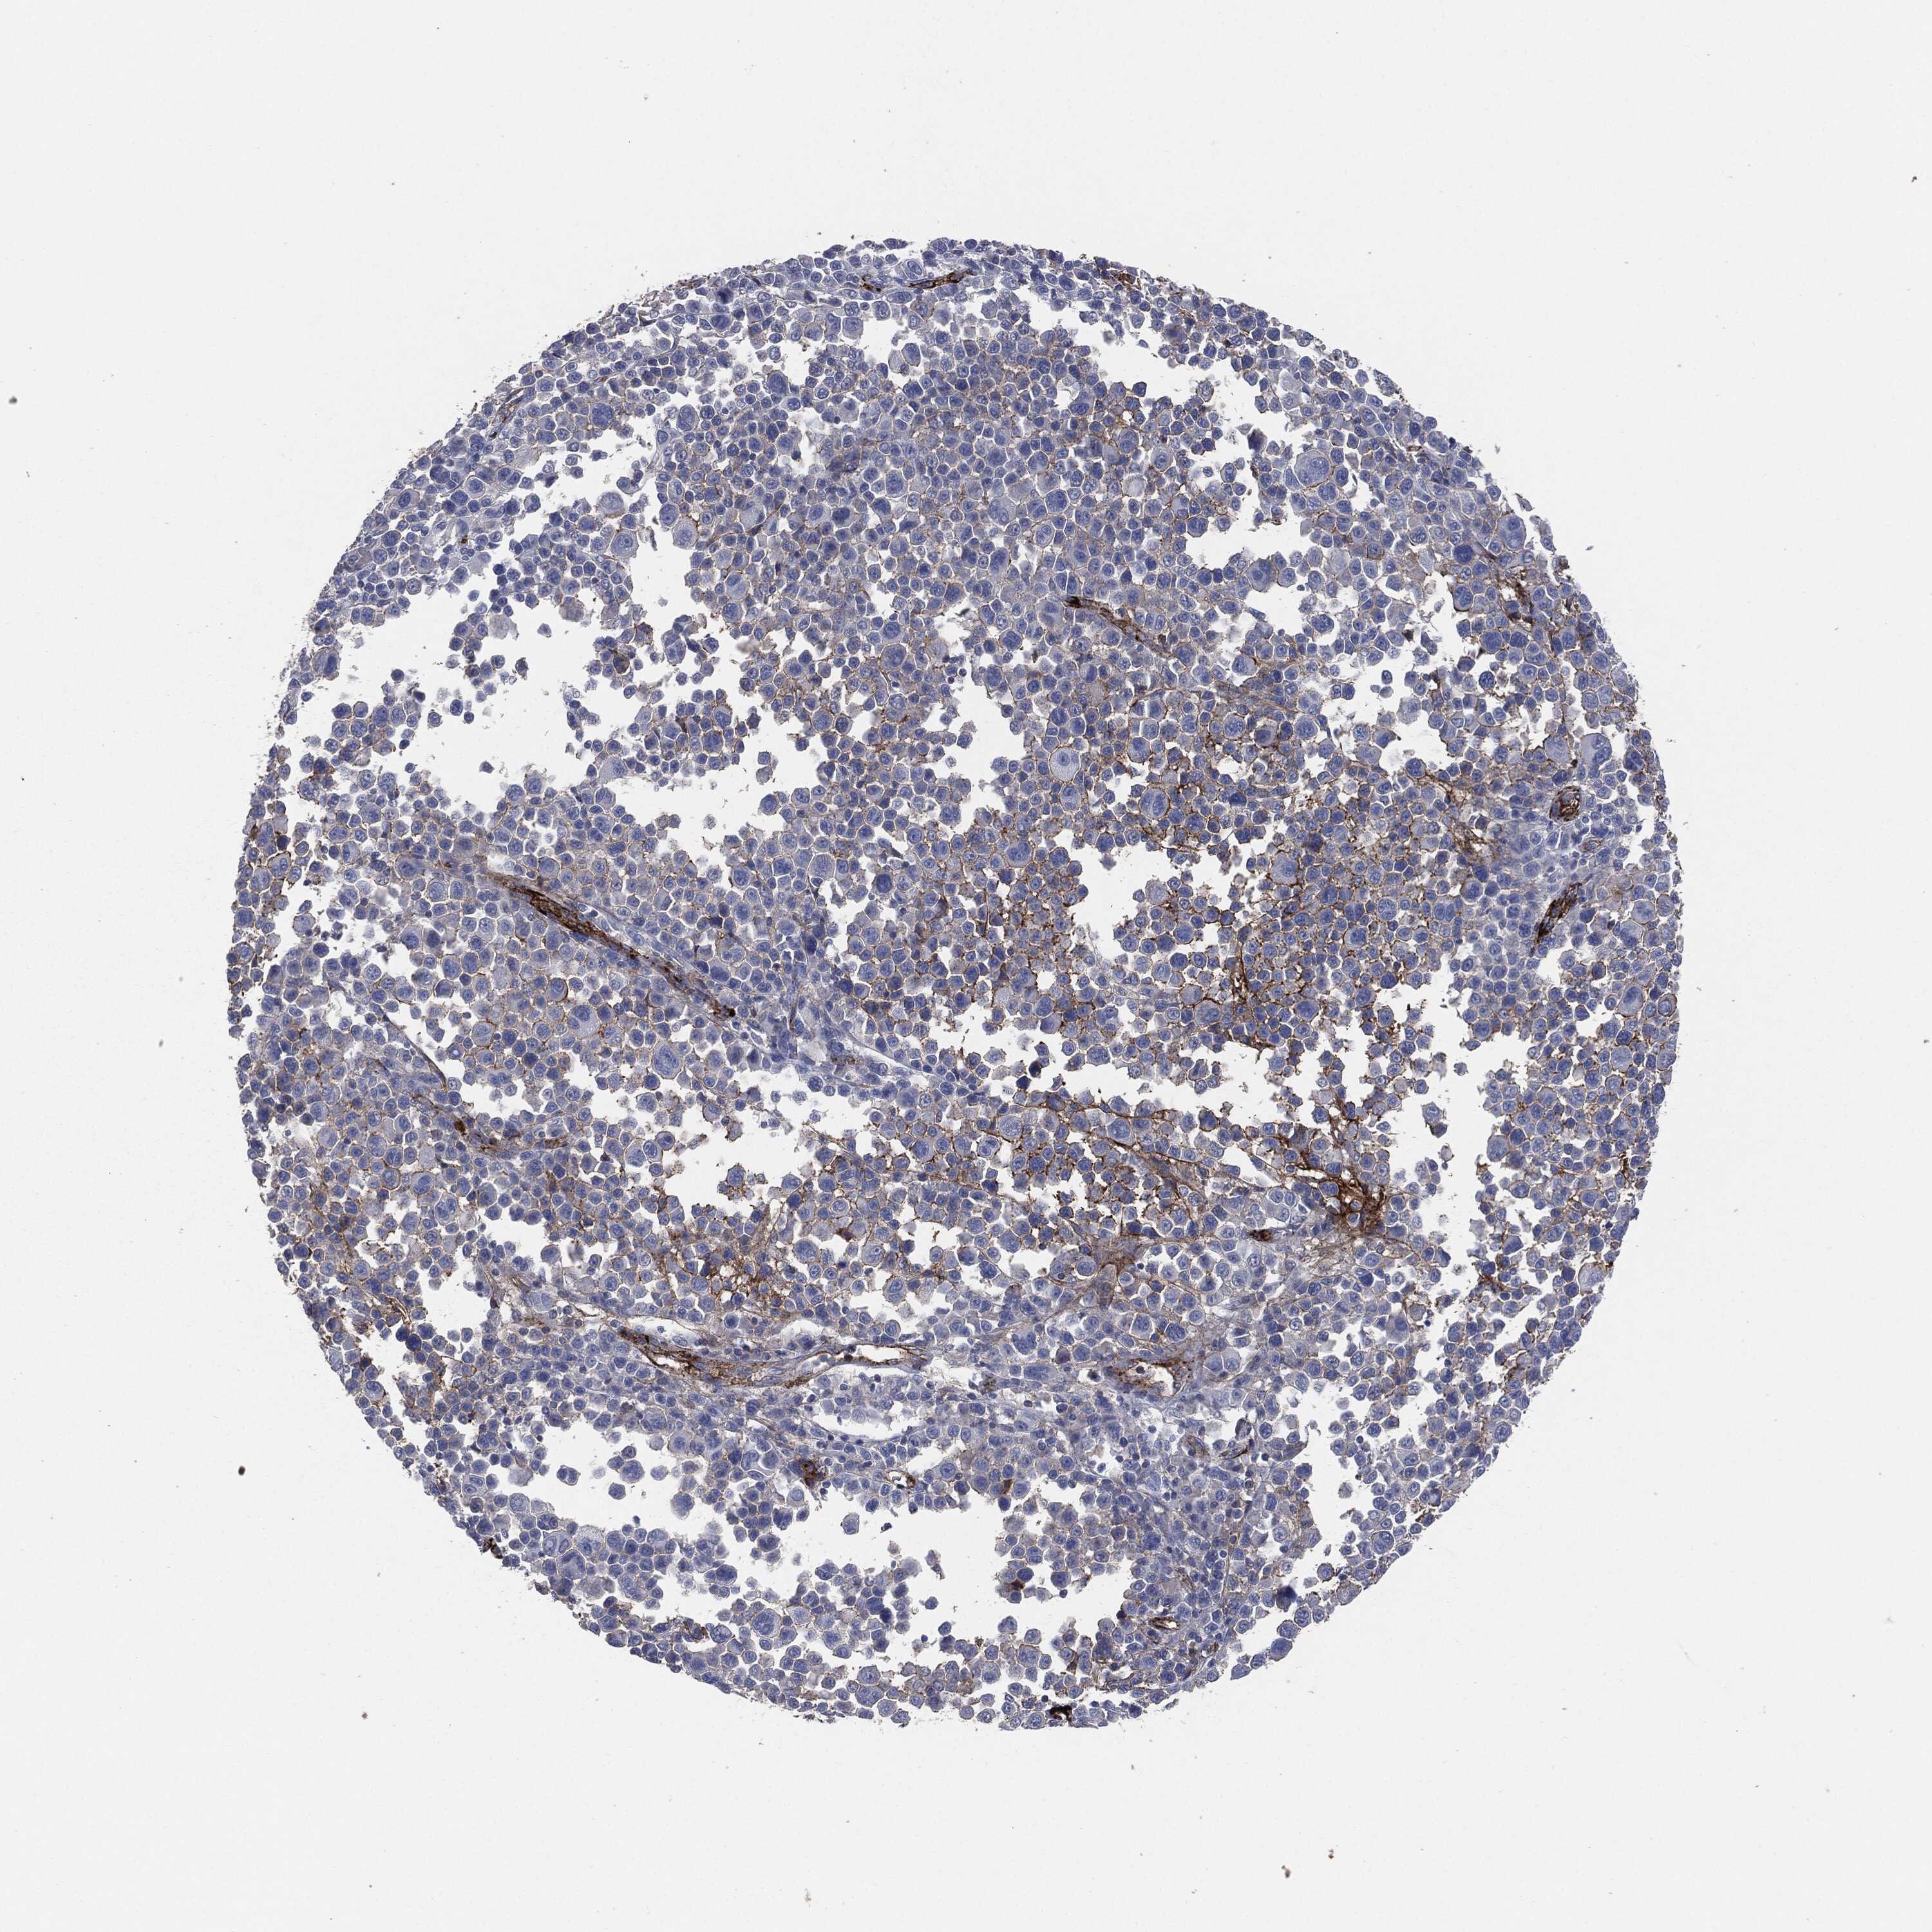

MELANOMA - Protein expressioni

A mouse-over function shows sample information and annotation data. Click on an image to view it in a full screen mode. Samples can be filtered based on level of antibody staining by selecting one or several of the following categories: high, medium, low and not detected. The assay and annotation is described here.

Note that samples used for immunohistochemistry by the Human Protein Atlas do not correspond to samples in the TCGA dataset.

Antibody stainingi

Antibody staining in the annotated cell types in the current human tissue is reported as not detected, low, medium, or high, based on conventional immunohistochemistry profiling in selected tissues. This score is based on the combination of the staining intensity and fraction of stained cells.

Each image is clickable and will lead to virtual microscopy that enables deeper exploration of all samples and also displays staining intensity scores, fraction scores and subcellular localization as well as patient and tissue information for each sample.

HPA049793

CAB016070

CAB080297

CAB080298

CAB080299

Malignant melanoma, NOS

Malignant melanoma, Metastatic site